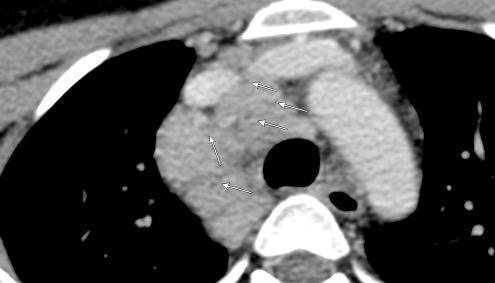

“ALAS DE MARIPOSA” (También. Bat´s wing) SIGNO

DE

Crónicas

Proteinosis alveolar

Silicosis

Sarcoidosis

Radiación

Neumonía organizada Muller Nl. High-yield Imaging.2010/Stern. ddx. 2011

Acumulación de material rico en proteínas y lípidos parecido al surfactante en el parénquima. Arquitectura conservada